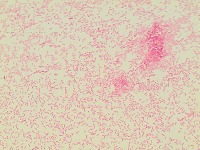

bacterial-image-classification Computer Vision Project

bacteriaclassification

Classes (78)

A description for this project has not been published yet.